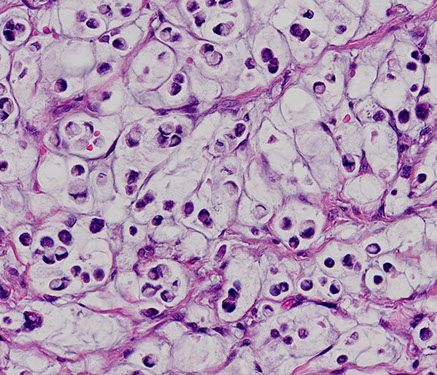

Signet-ring cell carcinoma of the colon

- uncommon histologic subtype of colon carcinoma (less than 5%)

- infiltrative epithelioid neoplasm extending transmurally into pericolonic adipose tissue/mesentery. Tumor cells demonstrate variable architectural patterns, including broad sheets and nests streaming through muscle and fibroadipose tissue, as well as single cell infiltrative growth. Individual cells are characterized by dense, hyperchromatic nuclei that are often compressed and eccentrically displaced by conspicuous intracytoplasmic mucin, seen in association with extracellular mucin surrounding groups of cells. Occasional cells with more marked cytologic atypia can be seen, as well as rare multinucleated giant cells within the muscularis propria

- Signet-ring cell carcinoma of the colon is classified as a primary colorectal adenocarcinoma with greater than 50% signetring growth pattern

- important pattern to recognize due to its worse prognosis and often higher stage at presentation

-  increased incidence of lymph node metastases, as compared to conventional colon adenocarcinomas